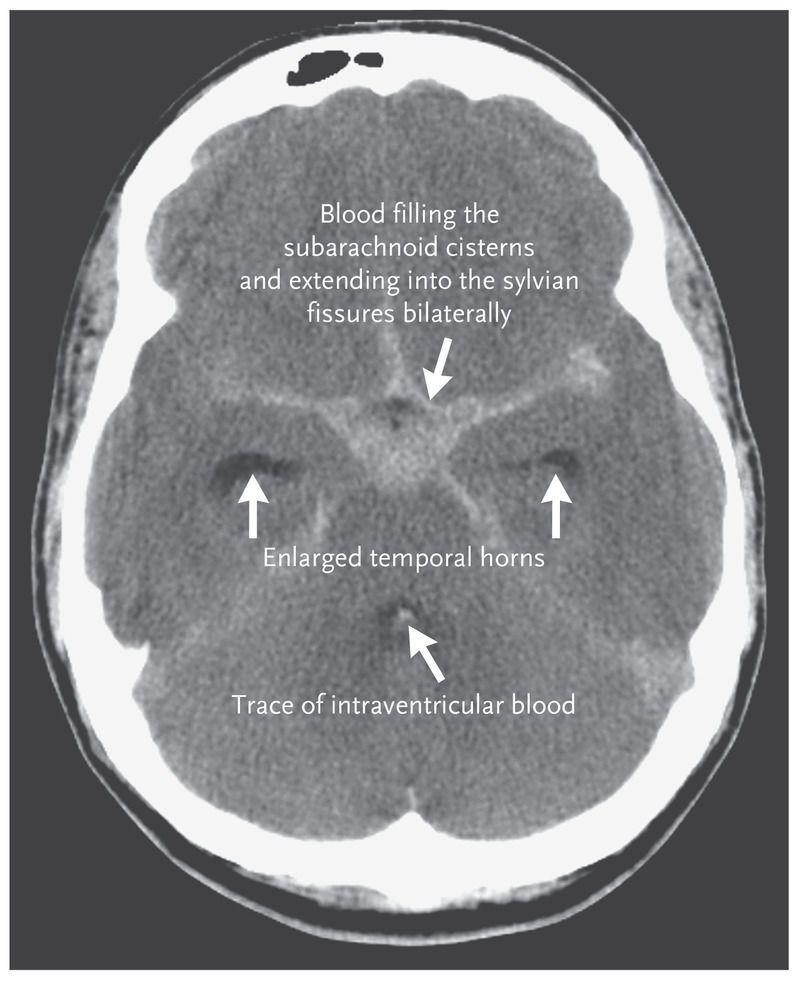

Subarachnoid hemorrhage is bleeding in the space between your brain and the surrounding membrane (subarachnoid space). Bleeding usually results from the rupture of an abnormal bulge in a blood vessel in your brain (Brain aneurysm). Sometimes an abnormal tangle of blood vessels in your brain (Arteriovenous malformation), Trauma or other events cause bleeding. A subarachnoid hemorrhage may lead to permanent brain damage or death if not treated.